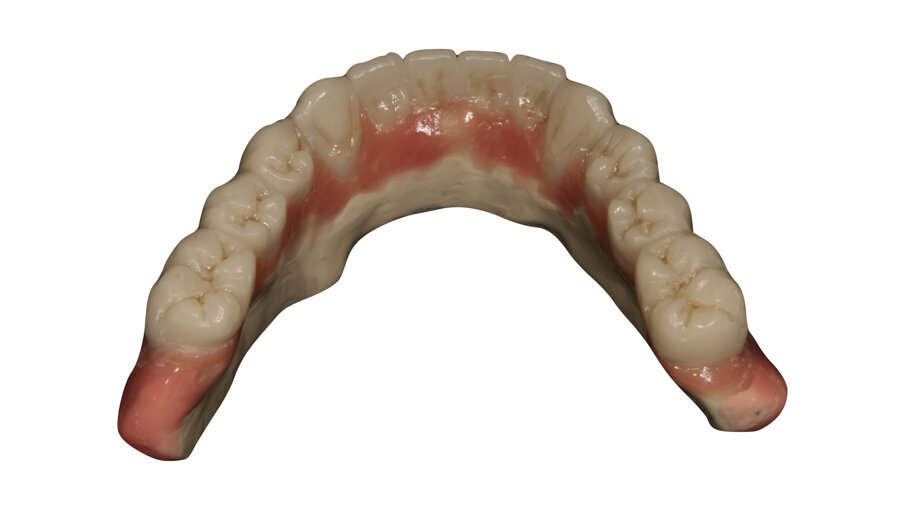

Figs. 15: Telescopic prosthesis with BRILLIANT Crios restorations. Occlusal view.

Figs. 16: Telescopic prosthesis with BRILLIANT Crios restorations. Bottom view.